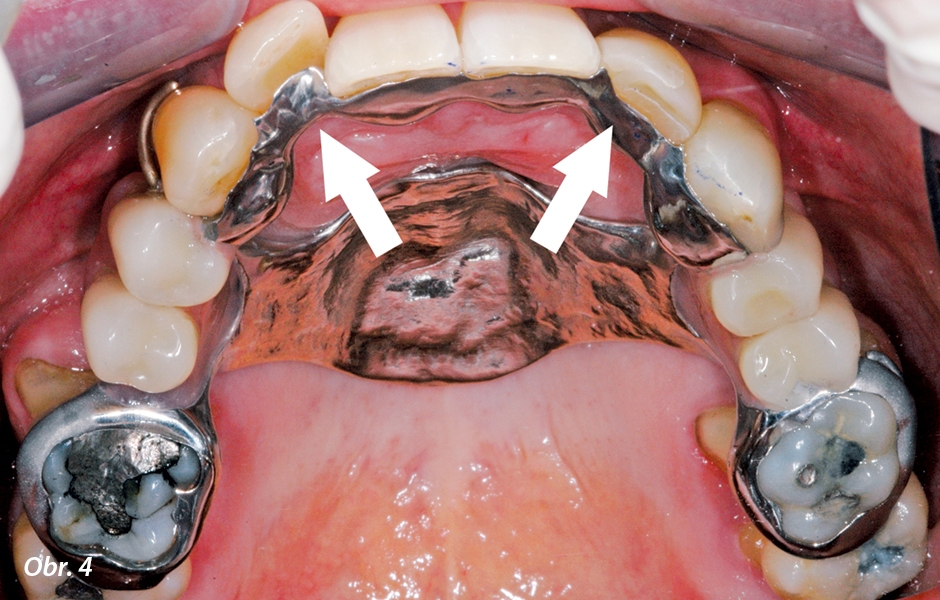

- Všestrannost designu: Za přítomnosti zubů s nejistou prognózou je možné navrhnout ČSN, kterou lze při ztrátě dalších zubů doplnit jejich náhradou. V případě mobilních zubů může ČSN sloužit jako definitivní dlaha (obr. 4).

Litá konstrukce byla navržena tak, aby působila zároveň jako definitivní dlaha pro horní frontální zuby a současně poskytla možnost pro doplnění dvou horních postranních řezáků